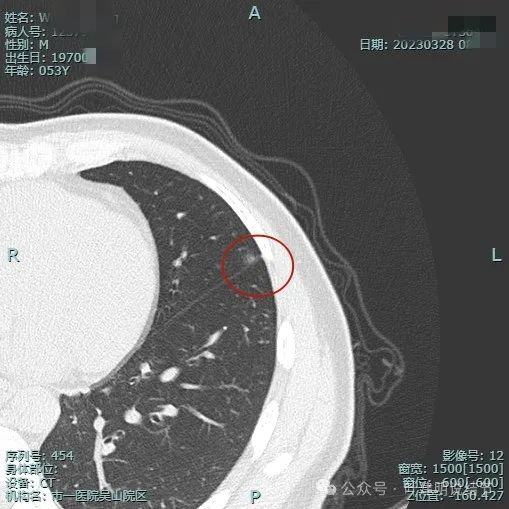

2023年3月影像展示:

病灶出现,密度淡,靠叶间裂较近,整体轮廓较为清楚。

密度纯,但不是太均匀,感觉稍不均,瘤肺边界清,贴胸膜近。

与叶间裂也是贴着的。

靶重建后见病灶密度不是很淡,轮廓较清,离叶间裂近但未见明显牵拉。

上图层面病灶贴着叶间裂,轮廓与瘤肺边界清楚,表面不光滑。

上图显得瘤肺边界稍模糊。

病灶似有极微细血管进入,贴着叶间胸膜但没有牵拉或明显凹陷。